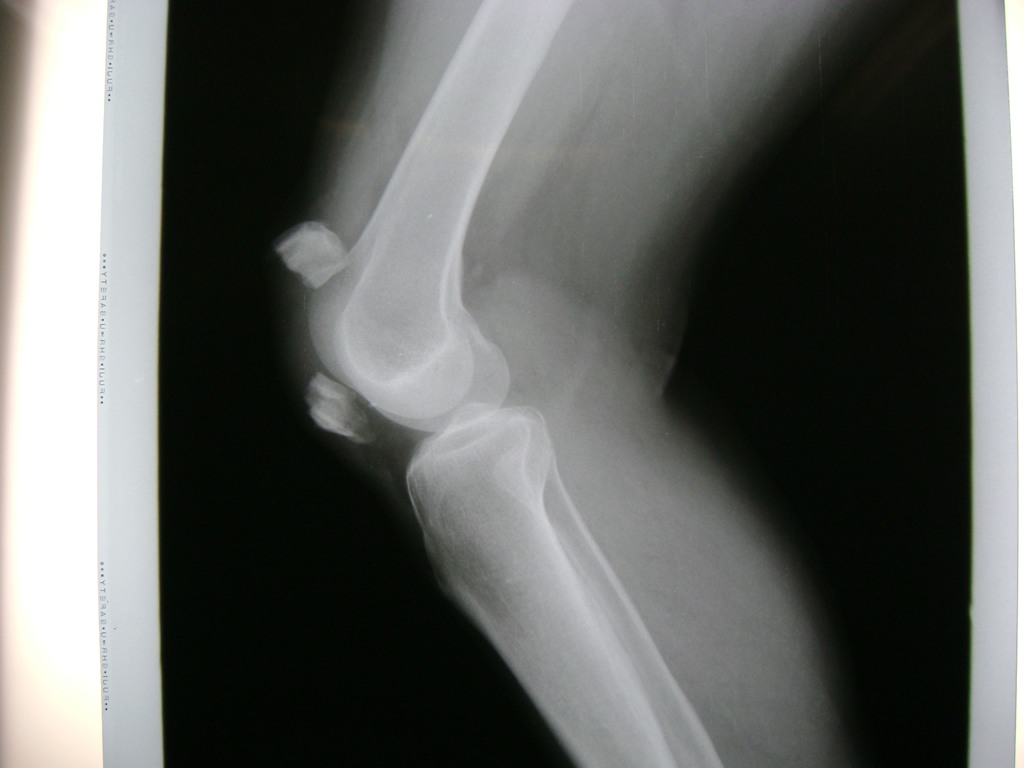

La artroscopia de rodilla es un cirugía en el cual la estructura interna de la articulación es examinada ya sea para realizar un diagnostico o para realizar un tratamiento, este procedimiento se realiza utilizando un instrumento parecido a un pequeño tubo llamado artroscopio.